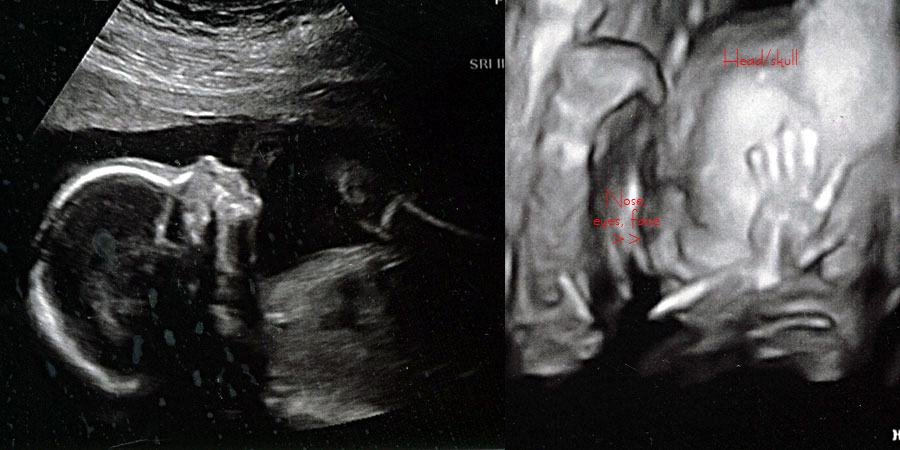

Today, to celebrate our 2-year anniversary, Scott and I got to get our first real glimpse at Baby H, who’s 21 weeks old. We are not finding out the gender of our baby, but are taking bets (see post from early September).

Baby H. is already making an impression as a squirmer and a disobedient little bugger, and because of this our 3D images didn’t turn out that great. They’re fairly distorted, but we included a couple anyway because the technology is still just so incredible. I was kind of bummed though that we couldn’t see more but baby just didn’t want to cooperate.